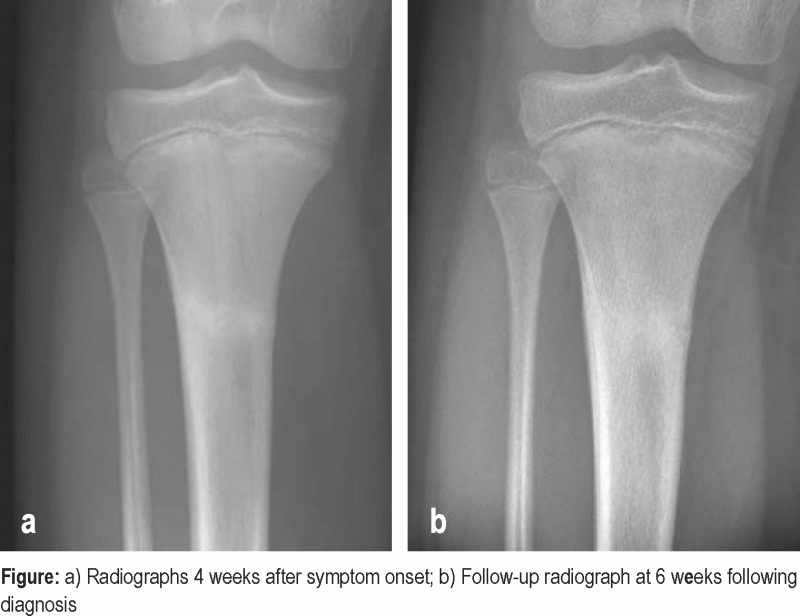

From www.researchgate.net

Stress fracture of the proximal tibia Download Scientific Diagram Stress Fracture Tibia Not Healing The vast majority of stress fractures will heal if treated correctly and promptly. Your provider will tell you how long you need to take a. A detailed overview of stress fractures. Stress fractures are tiny cracks in bones often caused by overuse or osteoporosis. Stop the activities that caused the stress fracture while you’re healing. This topic review will discuss. Stress Fracture Tibia Not Healing.